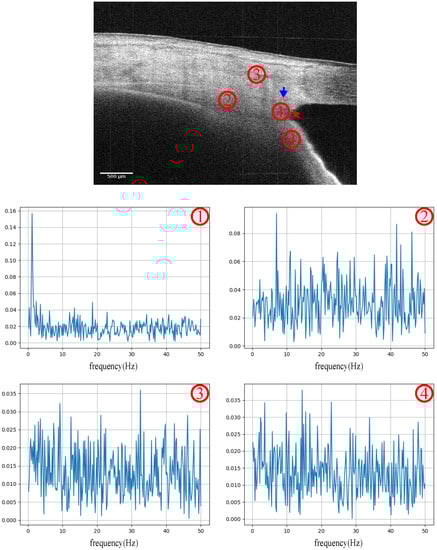

The OCT scanning position was located at the iridocorneal angle, both nasal and temporal. According to the real-time intensity images, the light incident direction was adjusted to the maximum iridocorneal angle degree. A series of cross-section images were recorded in 5 s. Furthermore, the phase signal was decomposed from the fast Fourier transform (FFT) of the OCT. The PhDiff was obtained simply by temporal subtraction of the contentious frames (pair of B scans). To remove the bulk motion, image registration based on the corresponding intensity image and phase compensation were implemented in advance. Figure 3 shows the frequency spectrum of signals sampled in specific regions of the iridocorneal angle, which included the TM-SC region, ciliary body, cornea and iris. Significantly, the fundamental frequency of the PhDiff signal in the TM-SC region was in the range of 1–2 Hz, the same as that of the heartbeat rate.

Figure 3. Frequency spectrum of the PhDiff signal sampled on the iridocorneal angle, including ➀: the trabecular meshwork and Schlemm’s canal adjacent region; ➁: the ciliary body region; ➂: the corneal region; and ➃: the iris region. The red arrow points to the trabecular meshwork, and the blue arrow points to the SC. The unit of the horizontal axis of the frequency spectrum graphic is Hertz.